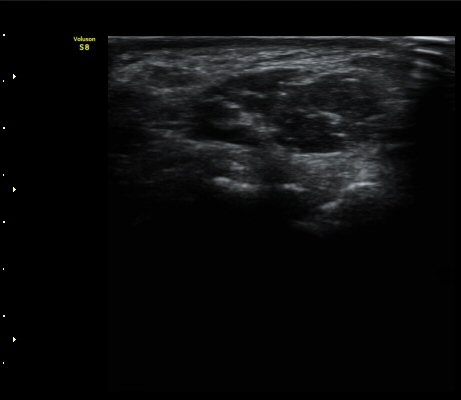

ÄÄÇ»ÅÍ ÃÔ¿µ»ó °¥°í¸®»À °¥°í¸® °ñÀýÀ» º¸ÀÓ(±×¸² 5, 6, 7).